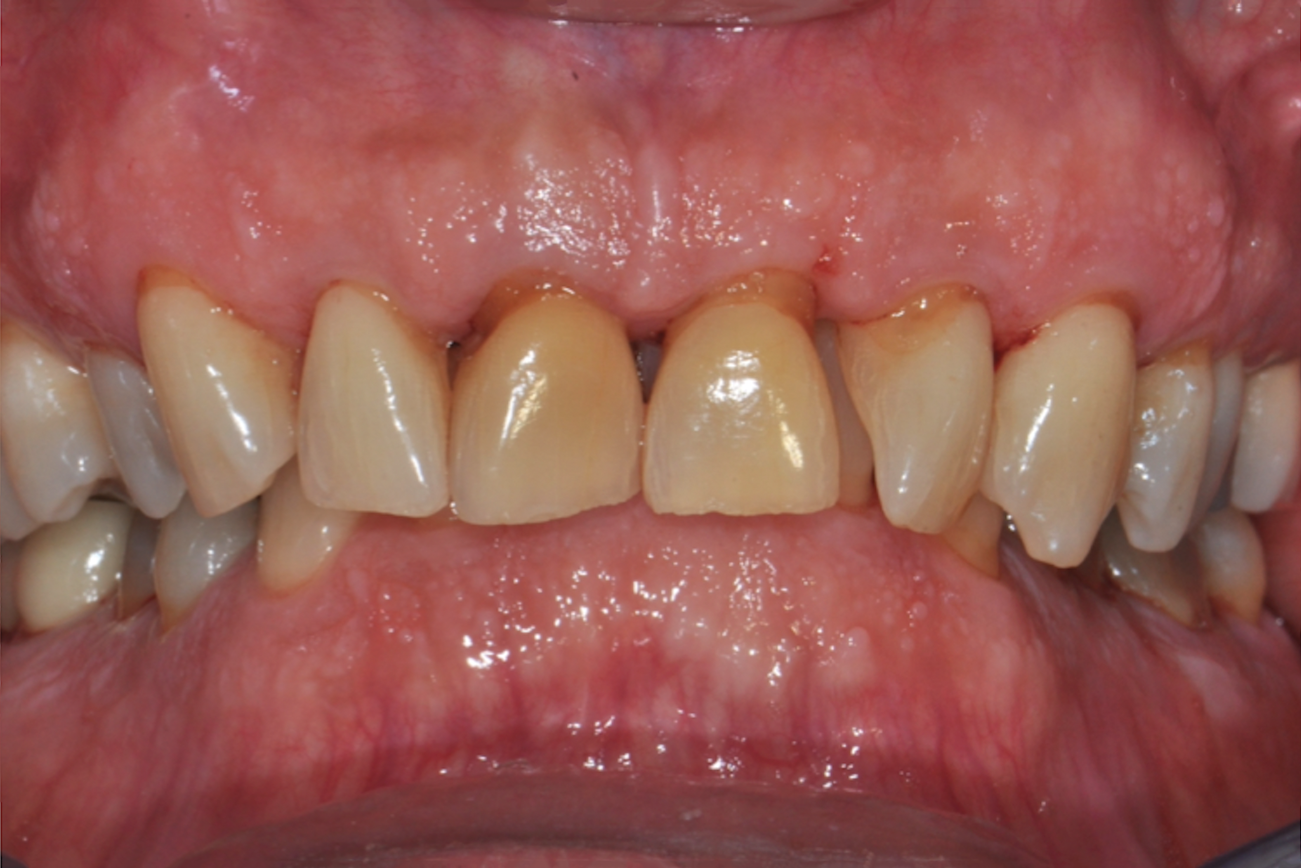

Fig 2. Pretreatment views: right lateral (Fig 2), frontal (Fig 3), and left lateral (Fig 4). Note: The maxillary right first molar (tooth No. 3) (Fig 2) would be identified as the most periodontally involved molar that was planned to be maintained.

Figure 2

Fig 3. Pretreatment views: right lateral (Fig 2), frontal (Fig 3), and left lateral (Fig 4). Note: The maxillary right first molar (tooth No. 3) (Fig 2) would be identified as the most periodontally involved molar that was planned to be maintained.

Figure 3

Periodontal examination revealed generalized BOP and PDs up to 9 mm in the maxillary and mandibular molars with multiple furcations in each molar (Figure 2 through Figure 7). He presented with class I mobility in many posterior teeth and class II mobility in teeth Nos. 3 and 9 (maxillary right first molar and maxillary left central incisor, respectively). The periodontist decided to score tooth No. 3 for the PRS, as this was the most periodontally involved molar that was planned to be treated and maintained (Figure 2 and Figure 8). This tooth (maxillary right first molar = score 1) presented with probing depths of 7 mm (score 1); three total furcation invasions (score 3) (mesial [degree II furcation], buccal [degree I furcation], and distal [degree II furcation]); and a class II mobility (score 2). The total PRS for tooth No. 3 was 8, representing a "guarded" prognosis. Based on this score, the likelihood of not losing any teeth to periodontal disease for 15 years was 81%, and for 30 years the likelihood was just 56% (Figure 9).7